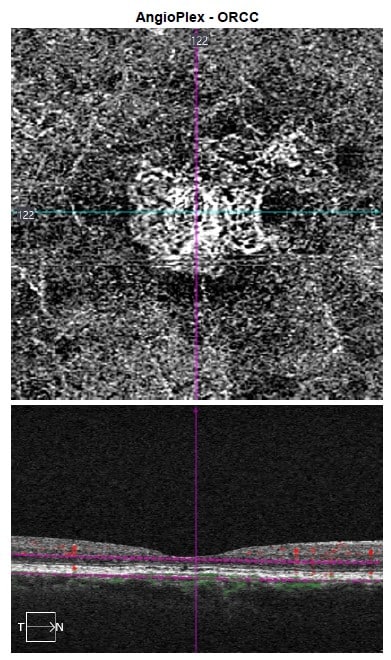

This finding, which represents a separation between Bruch’s membrane and the hyperreflective retinal pigment epithelium above it, can be suggestive of subclinical, nonexudative macular neovascularization (MNV). OCT angiography was obtained which confirmed the presence of a type 1 MNV (See Figure 2).

OCT angiography showed maturation of the MNV, with pruning of branching vessels and no change in the overall lesion size (see Figure 4).